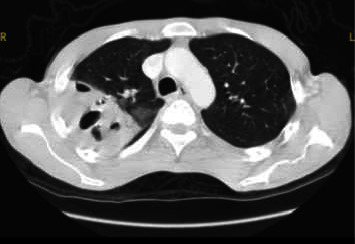

Rhodococcus equi is a rare human opportunistic pathogen that has been increasingly reported in recent decades. It mainly affects immunosuppressed patients, and in particular human immunodeficiency virus (HIV)-infected patients, where it typically presents as cavitary pneumonia. Early treatment with combined and effective antimicrobials and antiretroviral therapy after prompt diagnosis is essential to ensure an optimal outcome. We present a case series of three human Rhodococcus equi infections in HIV-infected patients with advanced immune suppression, treated at the University Hospital of Antwerp, Belgium.

Abstract Image